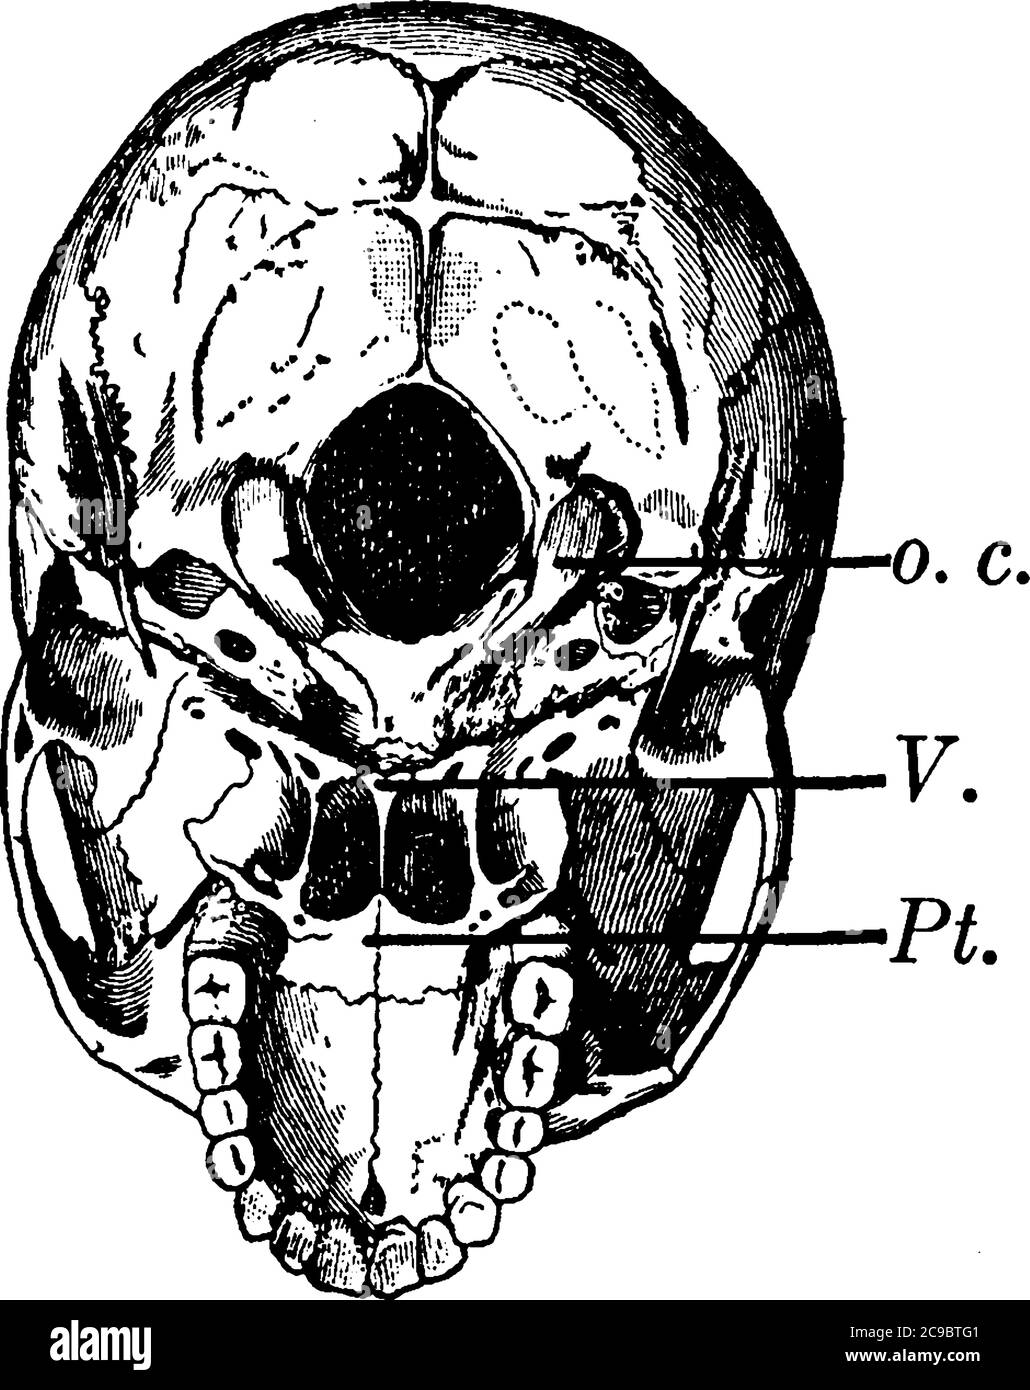

La mâchoire inférieure est déposée. Dans la partie inférieure de la figure se trouve le palais dur formant le toit de la bouche et entouré par la partie supérieure des dents, v Illustration de Vecteurhttps://www.alamyimages.fr/image-license-details/?v=1https://www.alamyimages.fr/la-machoire-inferieure-est-deposee-dans-la-partie-inferieure-de-la-figure-se-trouve-le-palais-dur-formant-le-toit-de-la-bouche-et-entoure-par-la-partie-superieure-des-dents-v-image367210369.html

La mâchoire inférieure est déposée. Dans la partie inférieure de la figure se trouve le palais dur formant le toit de la bouche et entouré par la partie supérieure des dents, v Illustration de Vecteurhttps://www.alamyimages.fr/image-license-details/?v=1https://www.alamyimages.fr/la-machoire-inferieure-est-deposee-dans-la-partie-inferieure-de-la-figure-se-trouve-le-palais-dur-formant-le-toit-de-la-bouche-et-entoure-par-la-partie-superieure-des-dents-v-image367210369.htmlRF2C9BTG1–La mâchoire inférieure est déposée. Dans la partie inférieure de la figure se trouve le palais dur formant le toit de la bouche et entouré par la partie supérieure des dents, v